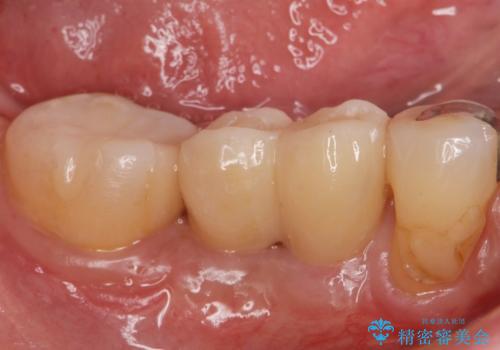

無事インプラントが入りました。

インプラント治療をしてもメンテナンスを怠っているとインプラント歯周炎になるリスクがあがるのでメンテナンスをお勧めします。